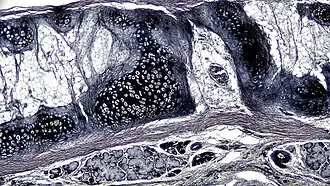

![]() Corte transversal de cartilagem elástica de mamífero

A cartilagem elástica é histologicamente semelhante à cartilagem hialina, mas contém muitas fibras elásticas amarelas dispostas em uma matriz sólida. Essas fibras formam feixes que aparecem escuros sob um microscópio. As fibras elásticas exigem coloração especial, pois quando coradas com hematoxilina e eosina (H&E) aparecem iguais à cartilagem hialina.[3] São usados corantes de Verhoeff van Geison (dando às fibras elásticas uma cor preta), mas corantes de fucsina aldeída, corantes elásticos de Weigert e corantes de orceína também funcionam.[3] Essas fibras conferem à cartilagem elástica uma grande flexibilidade, de modo que é capaz de suportar flexões repetidas. Da mesma forma que na hialina, um ou múltiplos condrócitos ficam entre os espaços (ou lacunas) nas fibras.[2] Os condrócitos representam apenas 2% do volume do tecido.[2] Os condrócitos e a matriz extracelular estão contidos em uma camada externa chamada pericôndrio[2] (que é uma camada de tecido conjuntivo denso não modelado que envolve a cartilagem independente da articulação).[3] É encontrada na epiglote (parte da laringe) e nos pavilhões auriculares (a parte externa da orelha de muitos mamíferos). As fibras de elastina coram em roxo escuro/preto com o corante de Verhoeff.